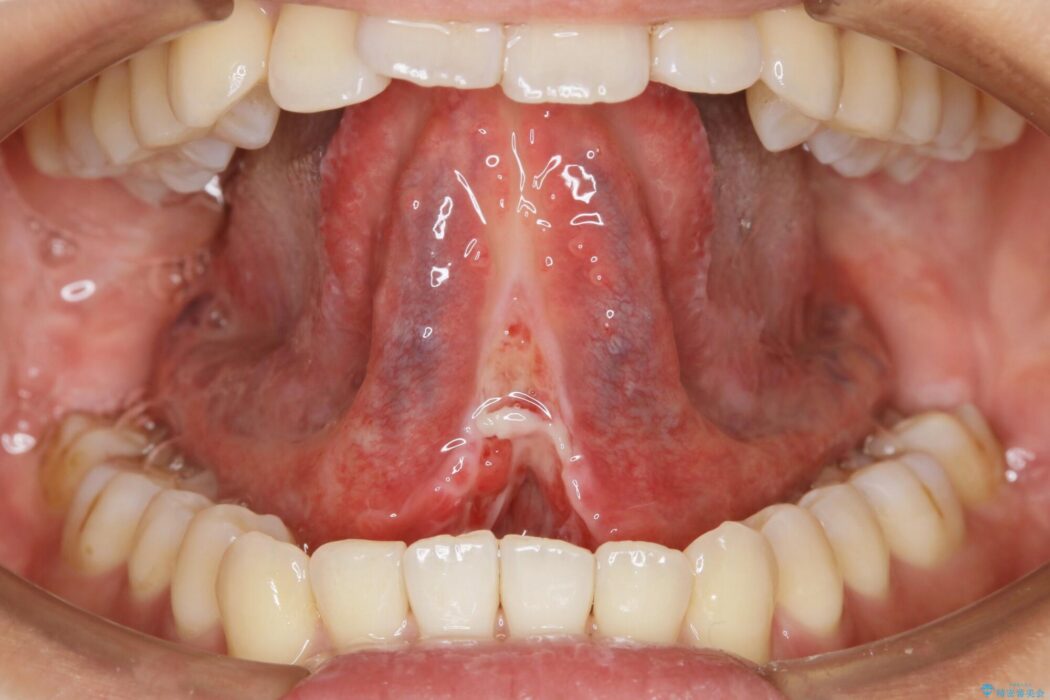

舌小帯切除術

舌小帯は舌の下面についているヒダのことを指します。個人によっても違いますが、舌小帯が短い・硬い場合は舌の動きが制限されてしまいます。それによって滑舌の悪さ、摂食・嚥下に影響を及ぼすことがあります。

このような舌小帯の異常の場合、「舌小帯切除術」を行うことがあります。

本症例ではレーザー機器を用いて手術を行いました。これにより従来のメスを使用する術式と比べて所要時間の短縮が図れ、かつ縫合を必要としないため術後の不快感も軽減することができます。

舌小帯切除術後、そのまま放置してしまうと切除した靱帯が元の短い状態で繋がってしまうことがあります。また手術前までで限られた範囲内のみで運動していた舌は通常の環境下の舌と比較して筋力か弱い傾向にあります。